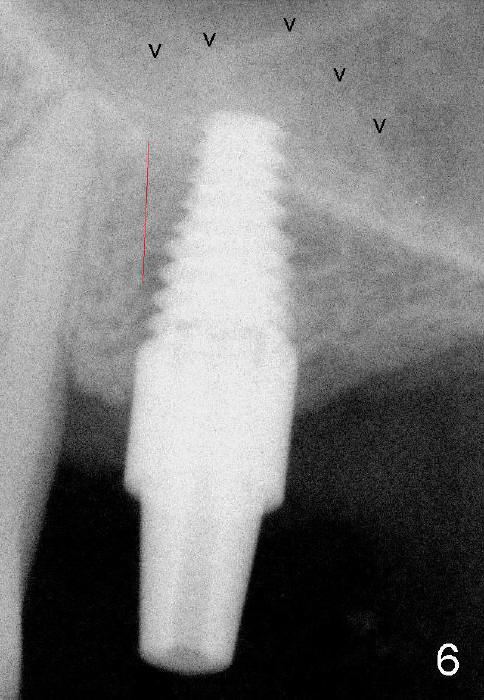

Fig.1: preop; Fig.4: 3.5x11 mm drill; Fig.5': 4.5x11 mm tap; Fig.6: 4.5x11 mm implant. Red line: original mesial apical outline of osteotomy. It shows that it is possible to change trajectory at late stage of osteotomy by changing angulation and position of burs, paying attention of orientation of tap and implant while inserting them.